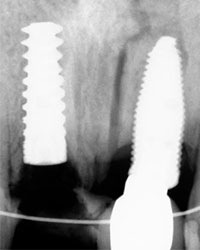

Paciente femenino a la cual le colocaron implante alto verticalmente, presentando a la vista una corona con un excedente de aproximadamente 5 milímetros, de porcelana rosa.

La paciente inconforme con los resultados nos visita, realizamos estudios radiográficos y tomográficos, encontrando que se perdió hueso verticalmente en el implante.

Decidimos hacer una corticotomia alveolar, dejando tejidos blandos en su lugar y cambiar la corona de cerámica por una corona de acrílico para cementar bien los brackets y poder empezar con la distracción.